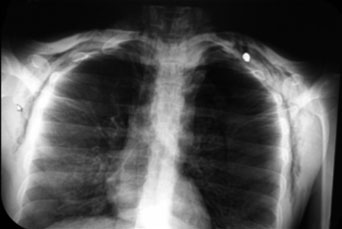

Paciente varón de 25 años de edad. Estilista, soltero, sin antecedentes alérgicos, quirúrgicos o crónico-degenerativos; ingresó al hospital a las 21:58 horas del 11 de agosto de 2014 por su propio pie, con el antecedente de haber sido agredido por terceras personas una hora previa a su ingreso. El paciente presentó una herida por proyectil de arma de fuego en el tórax anterior (figura 1), lo cual le produjo una considerable dificultad respiratoria y un aumento del volumen local. A su llegada el paciente estaba consciente, ansioso, cooperador y empleaba un lenguaje apropiado. Sus signos vitales eran de 130/80 de presión arterial, frecuencia cardiaca de 110 por minuto, frecuencia respiratoria de 28 por minuto, temperatura de 36 ºC y oximetría 96% al aire ambiente. Su vía aérea fue permeable en sedestación. Asimismo, el paciente presentó ventilación y movilidad torácica adecuadas ante la herida por proyectil de arma de fuego (orificio de entrada), la cual estaba a nivel infraclavicular derecho; no había hemorragias externas visibles y sus pulsos periféricos eran de buena intensidad, dado que eran rítmicos y simétricos.

La radiografía de tórax, además de presentar evidencia de hemoneumotórax izquierdo y neumotórax derecho, mostró enfisema subcutáneo severo (figura 2), por lo que fue necesaria la colocación de sondas endopleurales bilaterales.